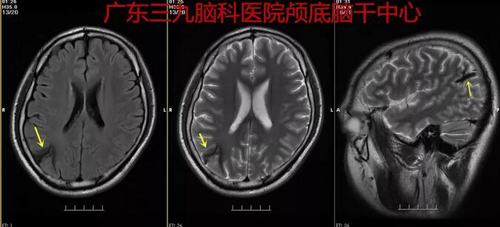

图1:术前MR 1.右侧顶叶软化灶形成,并含铁血黄素沉积,考虑为脑出血后遗改变;2.脑MRA检查提示右侧顶叶一较小的动静脉畸形,主要由稍增粗的右侧大脑中动脉一分支供血,可见增粗的引流静脉汇向上矢状窦区。